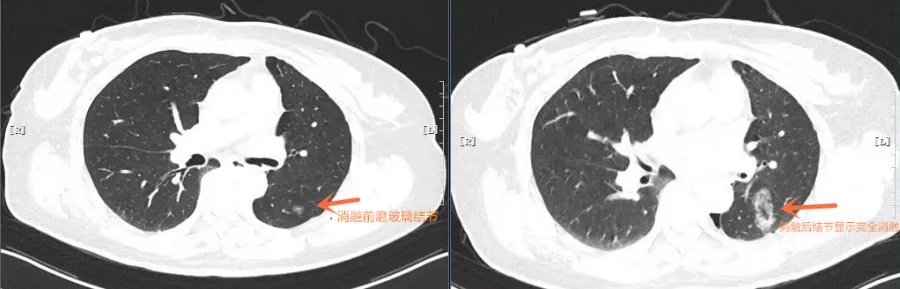

术中,肿瘤介入科王伟昱副主任在CT设备的引导下,准确无误地将消融探针送达结节位置。随后,通过控制能量输出,精确地消除病变组织,整个过程仅持续了几十分钟。

据悉,该院肺病科联手肿瘤六科(肿瘤介入科)已经成功开展多例肺结节微波消融术。微波消融技术作为一种针对肺部结节的微创精准治疗方法,广泛运用于肺部结节、早期肺癌及肺转移癌的根治及减容治疗。消融探针在CT引导下能够准确刺入结节内部,通过类似微波炉的加热原理,达到将结节“烧死”的目的。